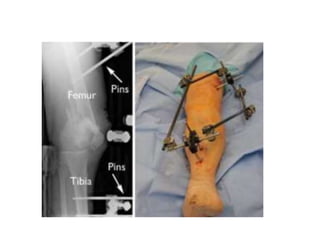

External fixation temporizing measure until soft

tissues permit internal fixation, or until patient is stable

avoid pin placement in area of planned plate placement if

possible